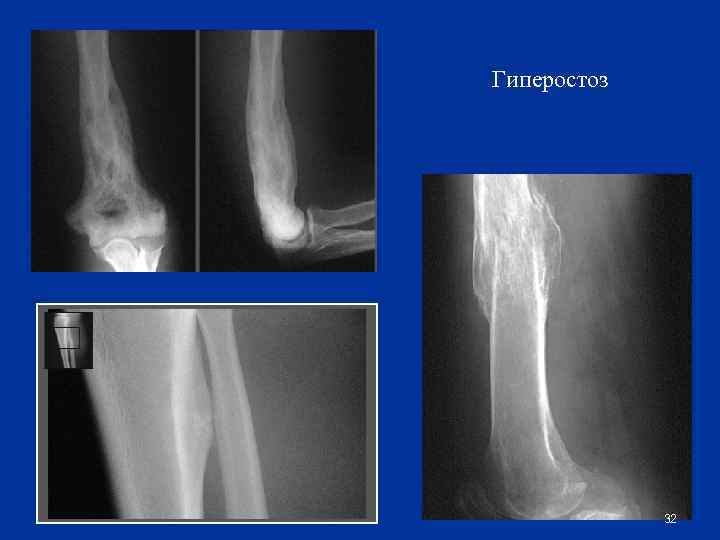

Утолщение кости (гиперостоз) n Функциональный гиперостоз n n n рабочая гипертрофия, заместительная (компенсаторная) гипертрофия Патологический гиперостоз n n первичный (идиопатический)- при врожденном гигантизме вторичный: n Воспалительный n Травматический n Гормональный n Токсический n прочие 31

Гиперостоз 32